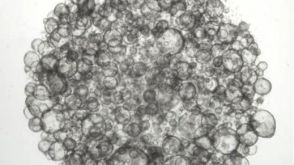

技术公告Forskolin-Induced Swelling of Human Intestinal Organoids Grown in IntestiCult™

技术公告Forskolin-Induced Swelling of Human Intestinal Organoids Grown in IntestiCult™产品类型:

Cell Culture Media and Supplements

细胞类型:

上皮细胞,肠道细胞